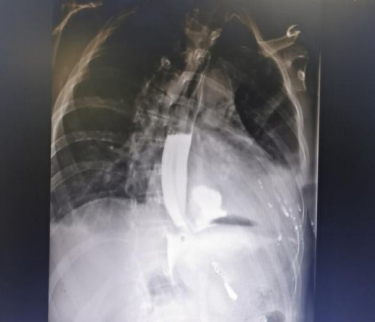

这里再给大家晒一个案例,这位患者是喝了白酒又去整第二场喝了一堆鸡尾酒,吐得来食管破裂,你看嘛,周围黑黢黢的那些组织就是破裂的食管腐蚀了,医生手术处理了很久才把这些组织取出来。

图片有丢丢吓人,大家慎点!